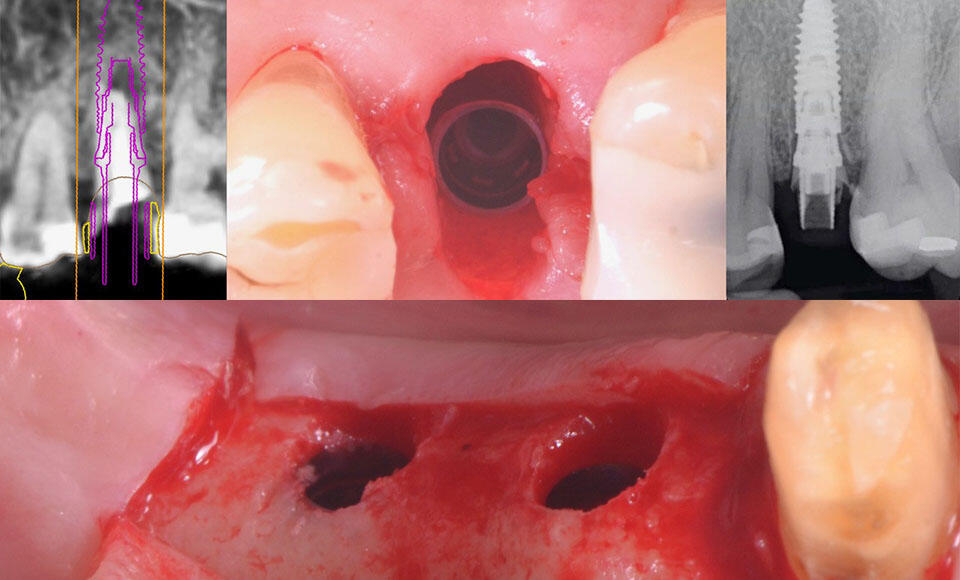

Foto: impianto sottocrestale